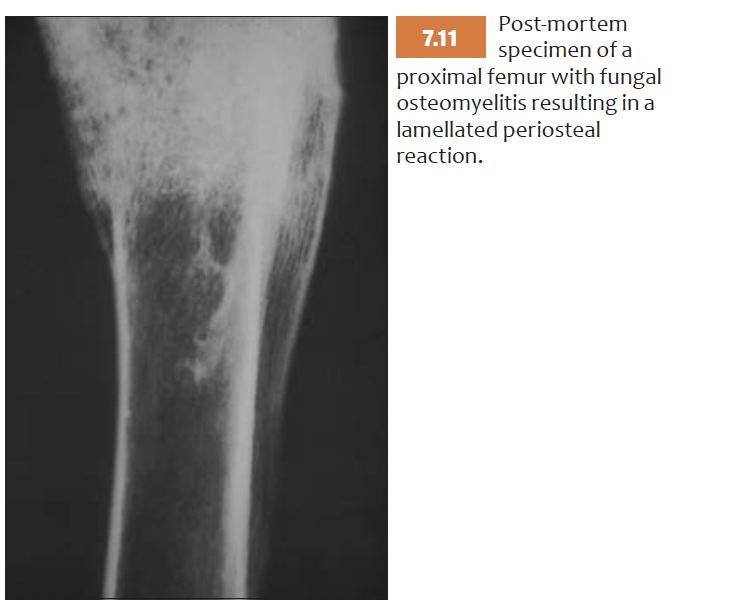

List features of Lamellated periosteal reaction